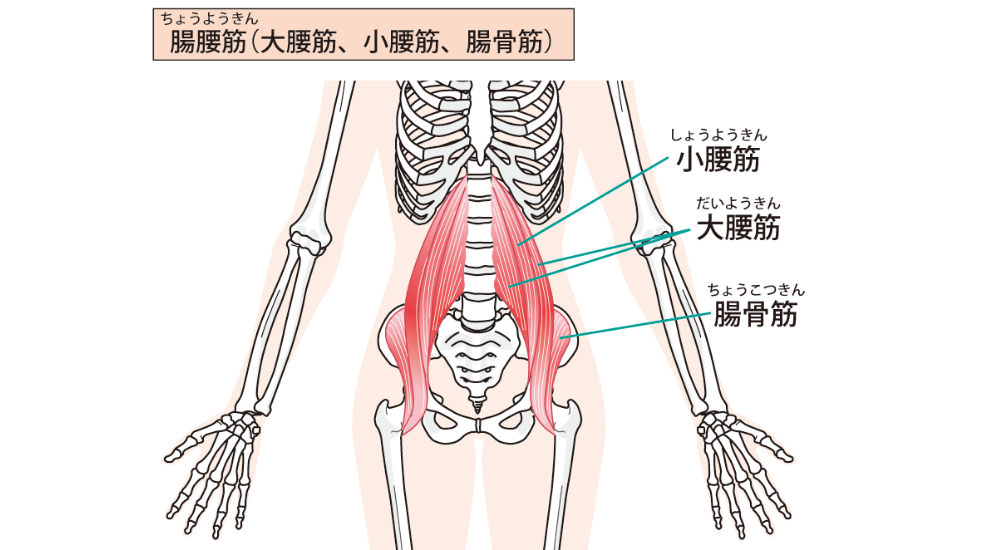

- お腹の奥と股関節の筋肉(大腰筋、腸骨筋):

ストレスや不安、トラウマなどと関連して緊張しやすい筋肉と言われます。ここが硬くなると、姿勢や骨盤のバランスを崩すだけでなく、自律神経の不調にも関与する可能性があります。

これらの筋肉の慢性的な緊張は、身体を常に「戦闘モード」に近い状態にさせ、自律神経のバランスを崩すことで、慢性的な疲労感や気分の落ち込みに繋がるのです。